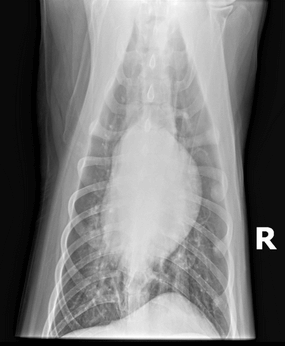

Chest x-rays were repeated to monitor for signs of NCPE in case this was due to electrocution, and they revealed a “progressive ventral pulmonary infiltrate likely reflecting pneumonia” with a distribution not typical for NCPE.

The tongue swelling improved and nearly resolved after ~3 days. The ulcerations stopped progressing and remained static. Soren’s respiratory rate and effort were closely monitored, he remained eupneic on room air and did not require oxygen supplementation. He did have a productive cough. His energy level improved, and his personality became more playful and interactive. Due to persistent fever and cough on Day 6, chest x-rays were repeated and showed a more severe ventral alveolar infiltrate due to progressive pneumonia.

X-ray of a dog’s chest taken from a lateral view, displaying lung and heart structures with some notable infiltrates.